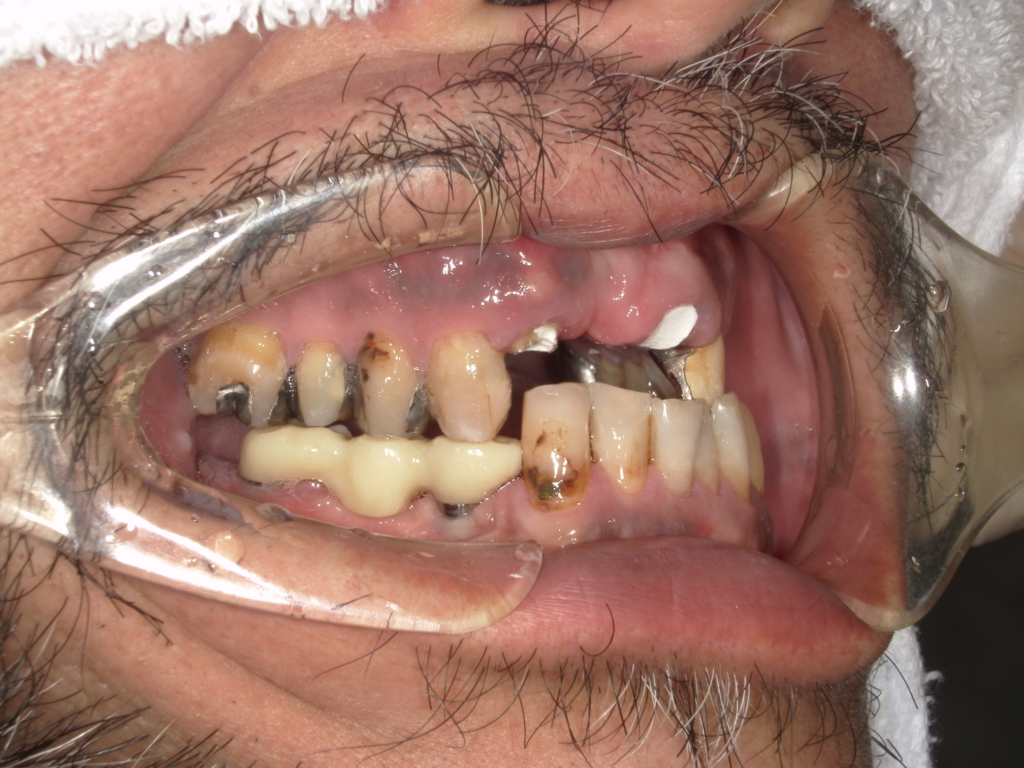

Y様インプラント実例 #44

左の上下の奥歯をインプラントで治療しています。

左下の奥歯は歯を抜くのと同時にインプラントの埋め込みを行っています。

被せものは上下、セラミックスで作っています。

治療前

治療後